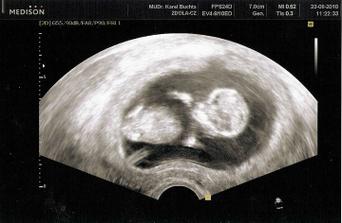

23.8.2010 první UTZ v ČR. Byli jsme zrovna 11tt+5 ale mrňousek odpovídal velikosti 12tt+1. NT Sreening dopadnul dobře a my jsme dostali první fotečky.